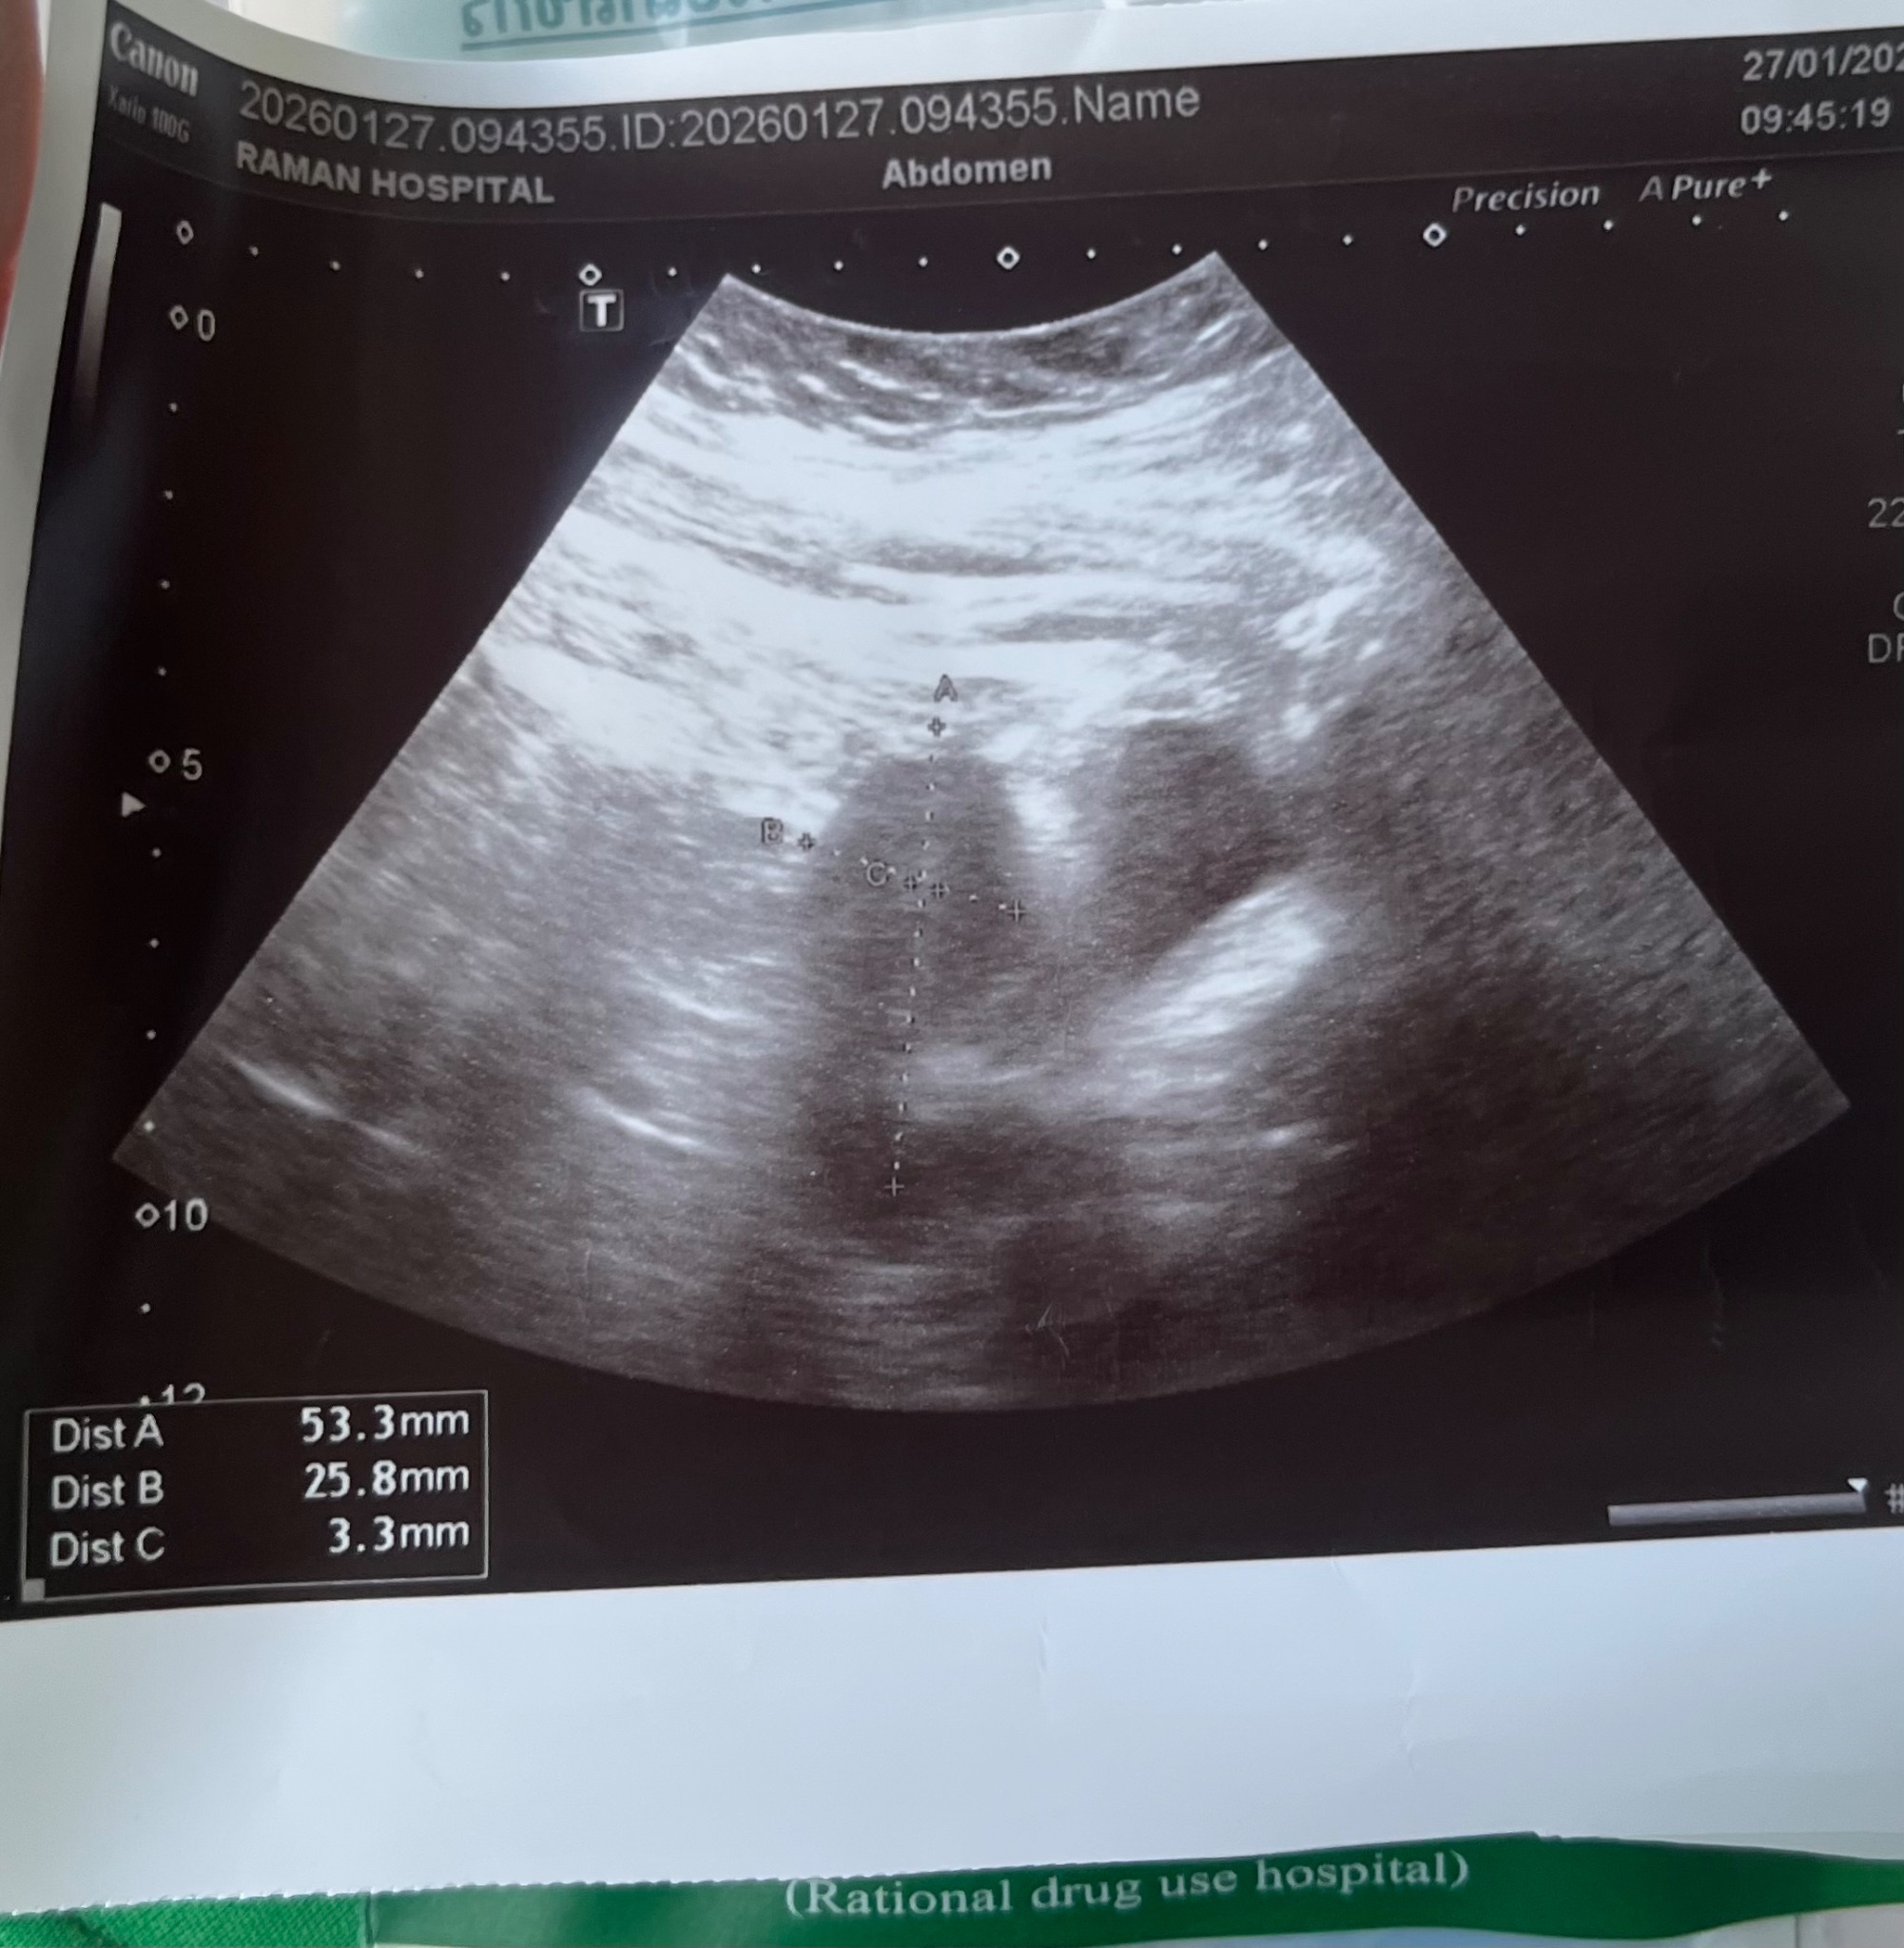

สวัดดีค่ะ เช้านี้เราตรวจขึ้นสองขีดจางๆ แต่พอไปโรงพยาบาลหมอบอกไม่ตั้งครรภ์

ไม่แน่ชัด อาจจะยังอ่อนๆอยู่ ช่วยดูหน่อยค่ะ หมอให้ภาพอัลตราซาวมา แบบนี้ท้องไหมค่ะ

สับสนมากตอนนี้ รอมา1ปีกว่า ก็ดีใจน่ะถ้าน้องมา ช่วยดูหน่อยน่ะคะ